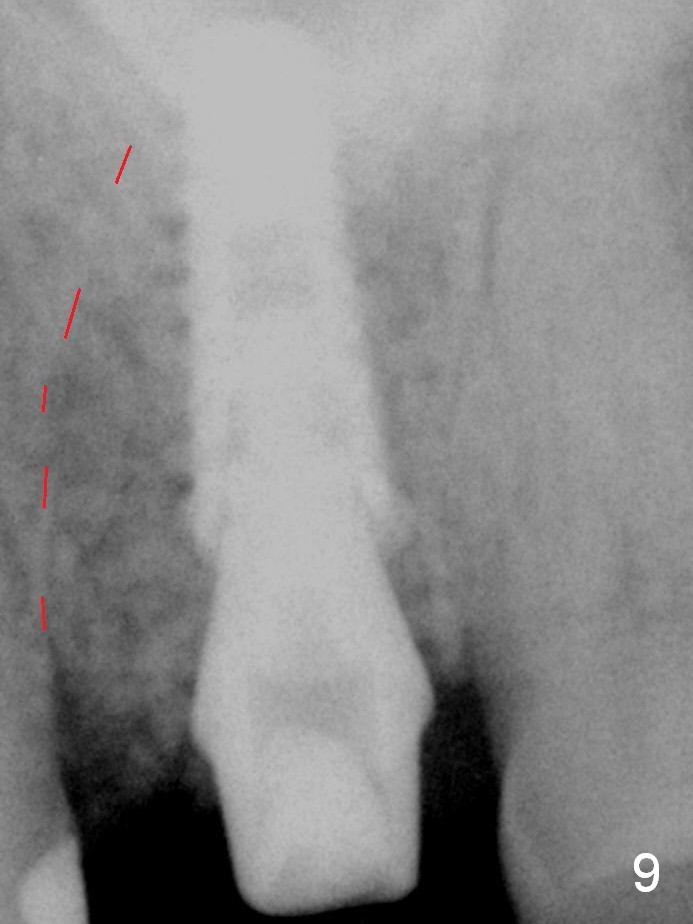

Continuously alternating use of MEs and drills leads to placement of a 5x11 mm implant with 30 Ncm insertion torque and sinus lift. After placement of bone graft (Fig.8 *) and 5x4(3) mm pair abutment (A), an immediate provisional is fabricated. Fig.9 is a PA taken higher than Fig.8 to show the sinus floor and the mesial wall of the socket (red dashed line).